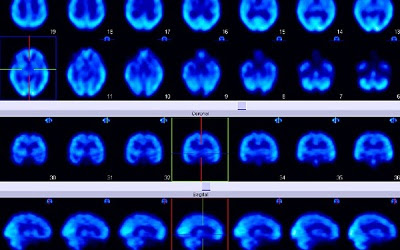

Comprueban el papel clave de una proteína en el metabolismo del colesterol cerebral

El colesterol es importante para el correcto funcionamiento de la corteza cerebral e hipocampo, que participan en procesos de aprendizaje y memoria.

El estudio de los científicos de la Universidad Católica Argentina (UCA) y del CONICET se realizó en cultivos de células cerebrales y ratones y podría conducir al desarrollo de nuevos tratamientos para dolencias neurodegenerativas.